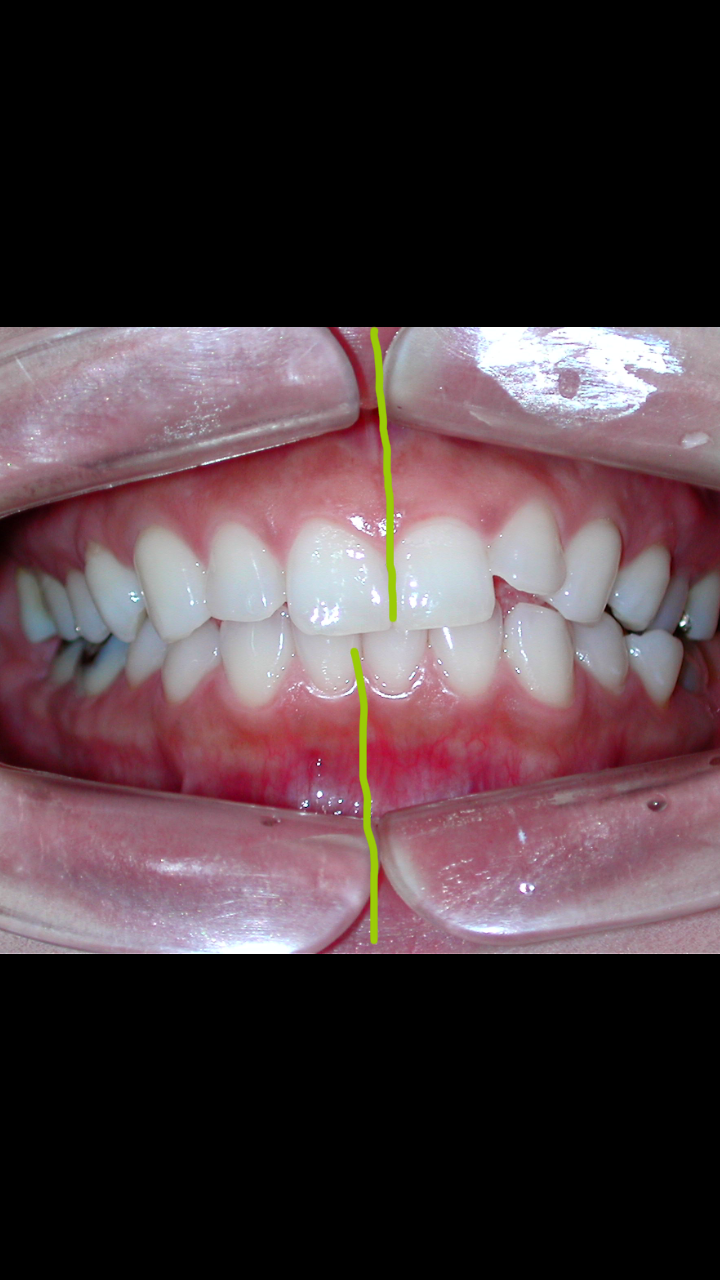

不正咬合は何が悪いのか Of くわはら矯正歯科医院 Bind

かみ合わせ 歯並び エド日本橋歯科

噛み合わせ 矯正治療でほうれい線としわが消える

噛み合わせ治療 水戸インプラントクリニックおおとも歯科 水戸市の歯科医院

48歳 女性 噛み合わせ 歯並び が悪い 前歯の被せを直して欲しい